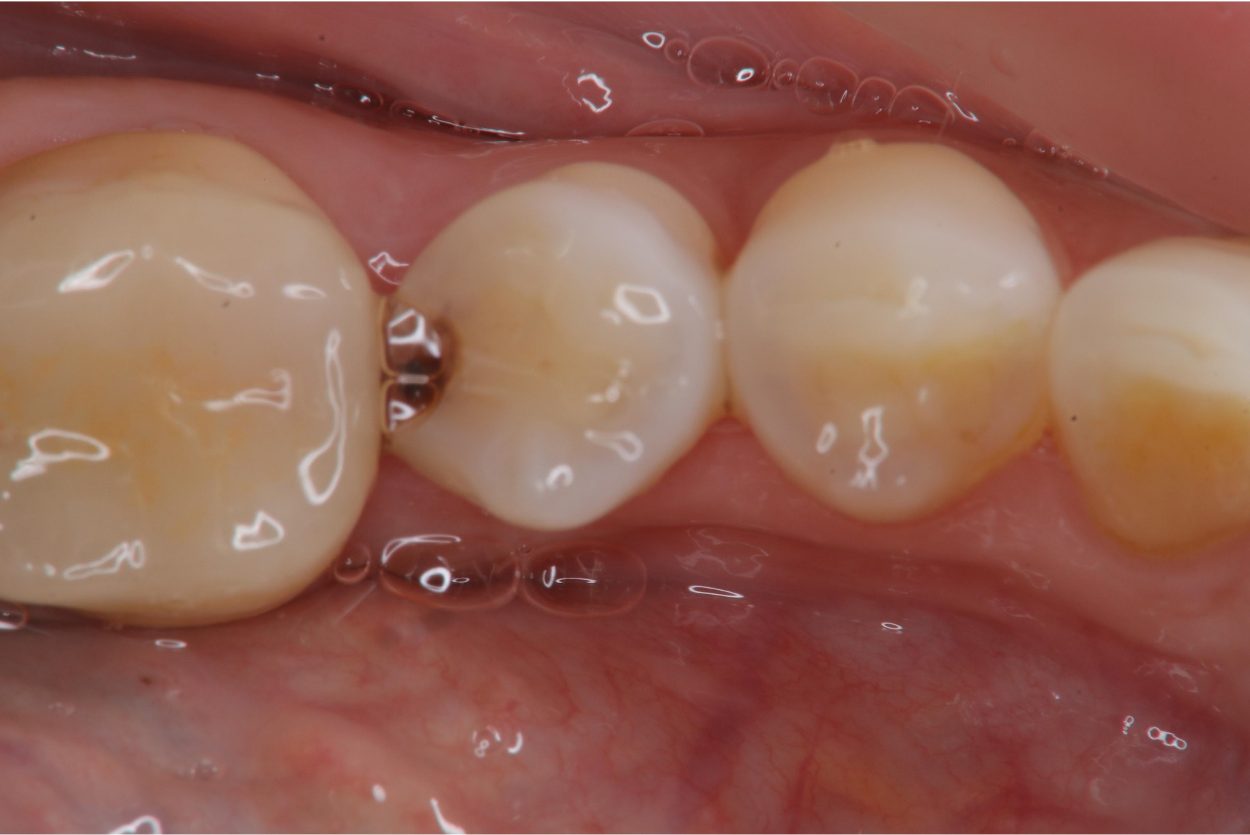

治療前,鄰接面蛀牙

1週後口內照